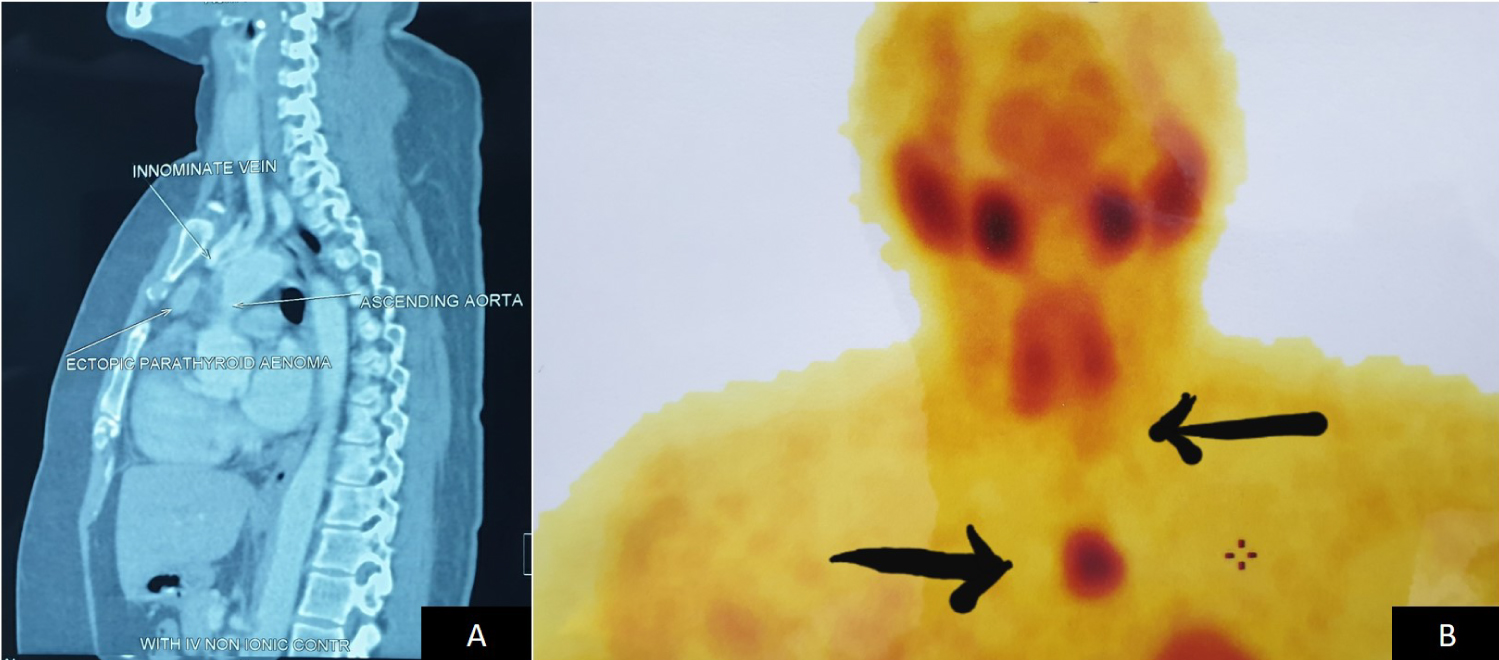

A 39-year-old woman was referred to us for generalized body ache of two months duration. She did not have any significant past medical or surgical history. Physical examination showed no abnormality. Routine investigations revealed elevated serum calcium levels 11.2 mg/dL (normal range 8.5-10.2 mg/dl). Thyroid function test was normal. Other blood investigations were normal. As a part of workup for hypercalcemia, serum parathyroid hormone (PTH) level was checked and it was elevated - 222.3 pg/ml (normal range 8-51 pg/ml). Serum magnesium was 2.33 mg/dl (normal range 1.5-2.5 mg/dl) and Vitamin D was 20 ng/ml (normal range 10-20 ng/ml). In view of raised serum PTH level, Sestamibi scan was done which revealed an intrathoracic ectopic parathyroid adenoma in addition to left inferior parathyroid adenoma. CT scan of neck and chest with contrast showed a left inferior parathyroid adenoma and an ill-defined enhancing lesion in the anterior mediastinum in pre vascular space measuring 2.6 × 2.5 × 1.2 cm, lesion was beneath the sternomanubrium joint level inferior to innominate vein and anterior to ascending aorta. In order to confirm, Tc99mm Sestamibi SPECT (Single Photon Emission Computed Tomography) was performed which was suggestive of ectopic parathyroid adenoma in intrathoracic region and left inferior parathyroid adenoma (Figure 1). Patient was admitted for excision of intrathoracic ectopic parathyroid adenoma and left inferior parathyroid adenoma. Under general anaesthesia, surgery was performed in 2 steps. Through a skin collar crease, incision skin flaps were raised. Sternothyroid and sternohyoid muscles were retracted. Excision of left inferior parathyroid adenoma was carried out after identifying and preserving the left recurrent laryngeal nerve. The other three parathyroid glands were explored and they all appeared normal. Since the mediastinal adenoma was inferior to the Innominate vein and in front of the ascending aorta, excision of the same was not attempted through the cervical incision. Anterior mediastinal adenoma was exposed via median sternotomy using a midline incision extending from the suprasternal notch to the xiphoid process. Mediastinum was entered after cutting the sternum using a pneumatic sternal saw. There was a circumscribed adenoma seen inferior to the innominate vein and in front of ascending aorta which was excised in toto along with the tract connecting it to the left inferior parathyroid adenoma and were sent for histopathological examination (Figure 2). 12hrs after surgery, serum PTH level dropped to 13.8 pg/ml and 24hrs after surgery, serum calcium level dropped down to 8.1mg/dL. Patient had developed symptoms of hypocalcemia in the post-operative period and was treated with intravenous calcium gluconate.

Figure 1: A) CT scan showing an Ill-defined enhancing lesion in the anterior mediastinum in pre vascular space beneath the sternomanibrium joint level inferior to innominate vein and anterior to ascending aorta; B) Sestamibi scan was suggestive of an intrathoracic ectopic parathyroid adenoma along with a left inferior parathyroid adenoma. View Figure 1